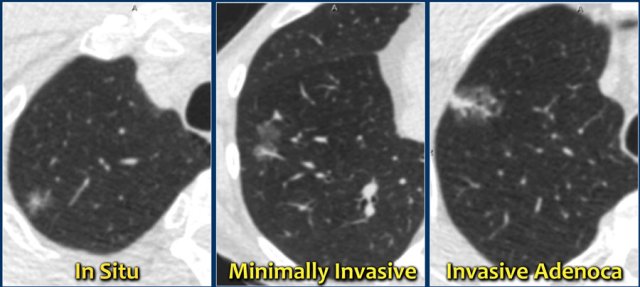

However, persistent subsolid nodules often represent pathology in the adenocarcinomatous spectrum.

Subsolid nodules in the adenocarcinomatous spectrum were formerly known as bronchoalveolar carcinoma or BAC.

This terminology should no longer be used.

A new pathology-based classification for adenocarcinoma was introduced in 2011 and this current classification makes distinction between:

1. Adenocacinoma in situ.

2. Minimally invasive adenocarcinoma.

3. Invasive adenocarcinoma.